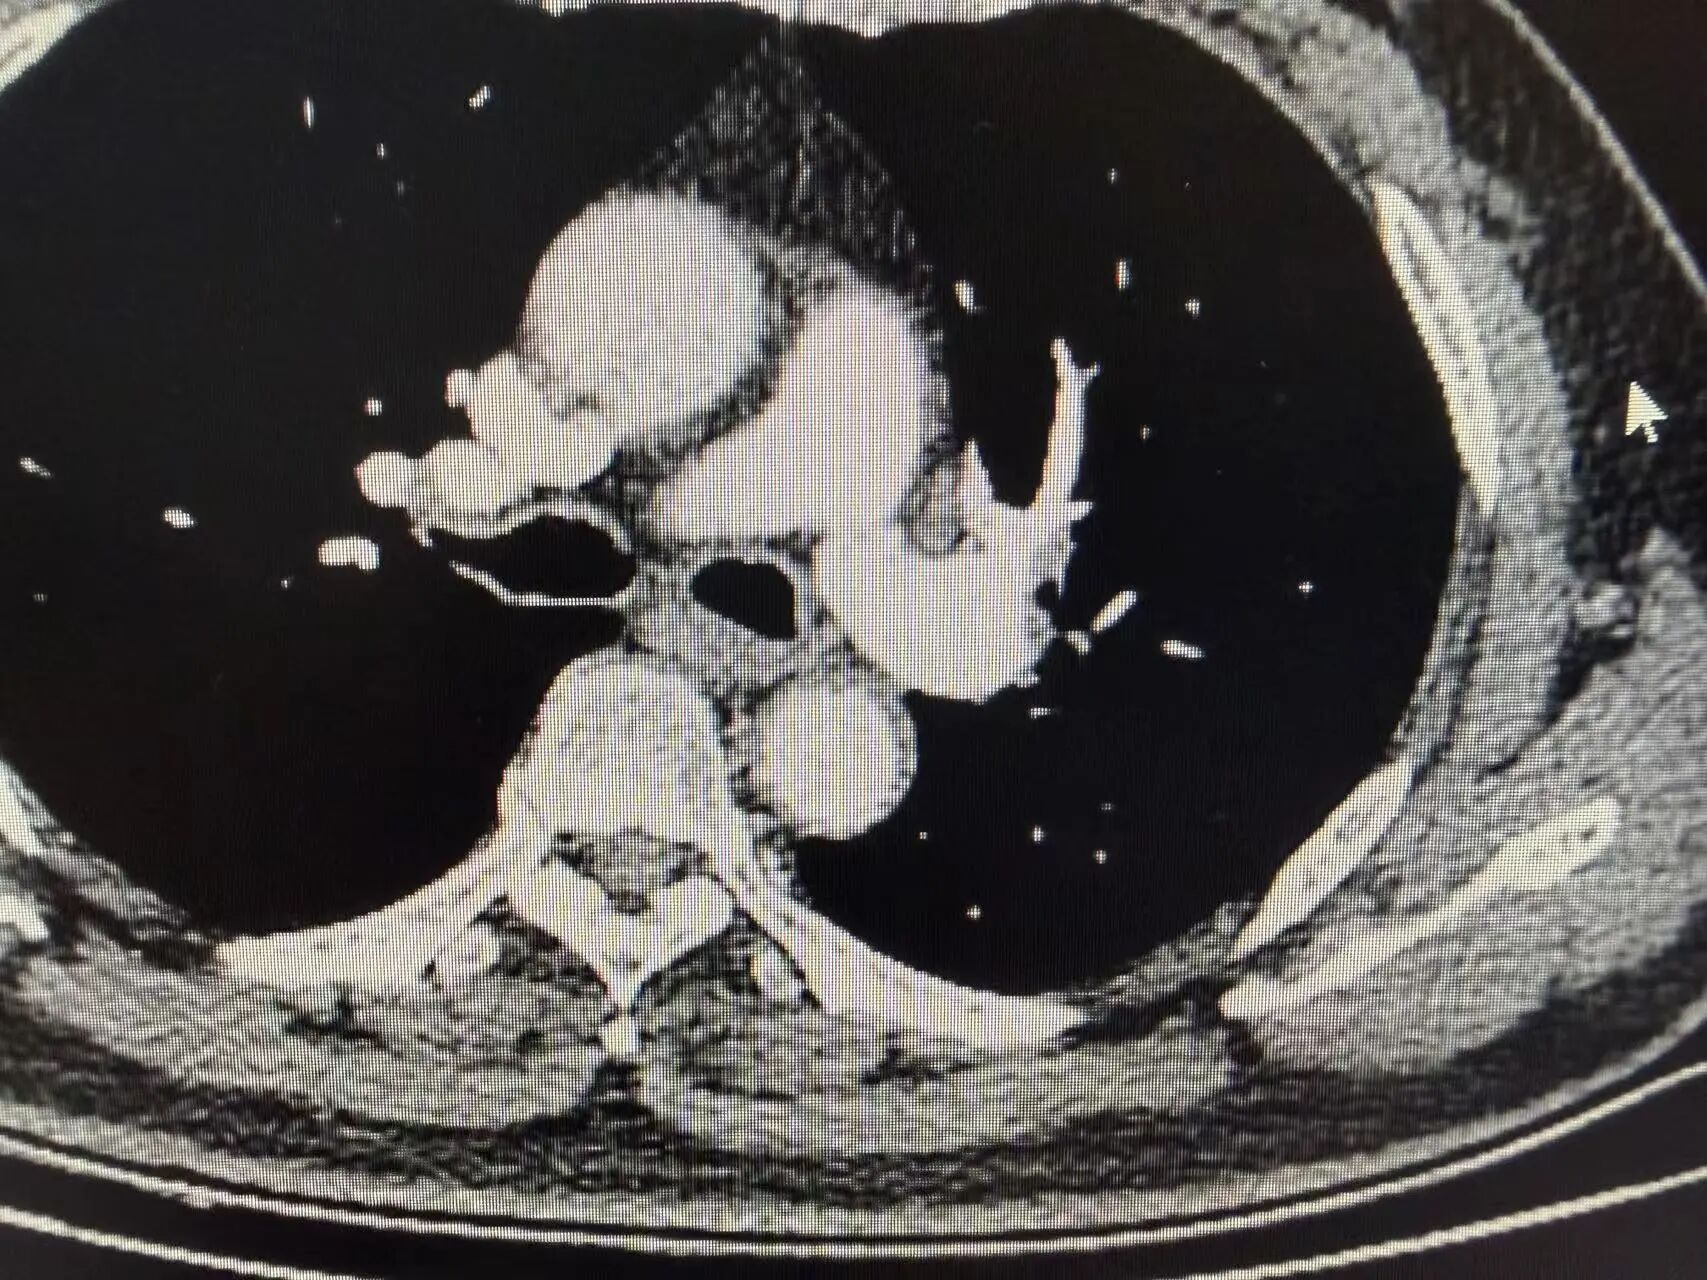

胸部增强CT结果显示:左上肺可见明显占位性病变,体积较大,同侧肺门淋巴结伴随肿大。后续穿刺病理活检明确诊断为肺鳞状细胞癌,结合淋巴结转移情况,分期为局部晚期(Ⅲa期)。

新辅助治疗前CT影像